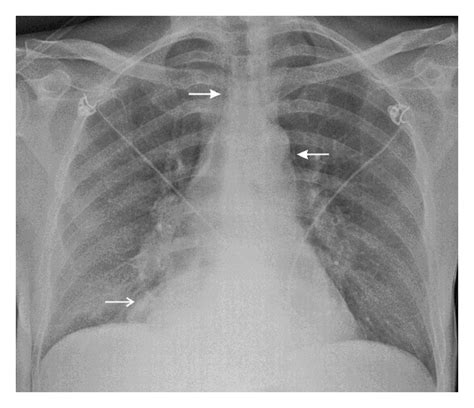

A systematic review of contemporary evidence on SARS-CoV-2 ...

A systematic review of contemporary evidence on SARS-CoV-2 ... from www.avicennajmed.com